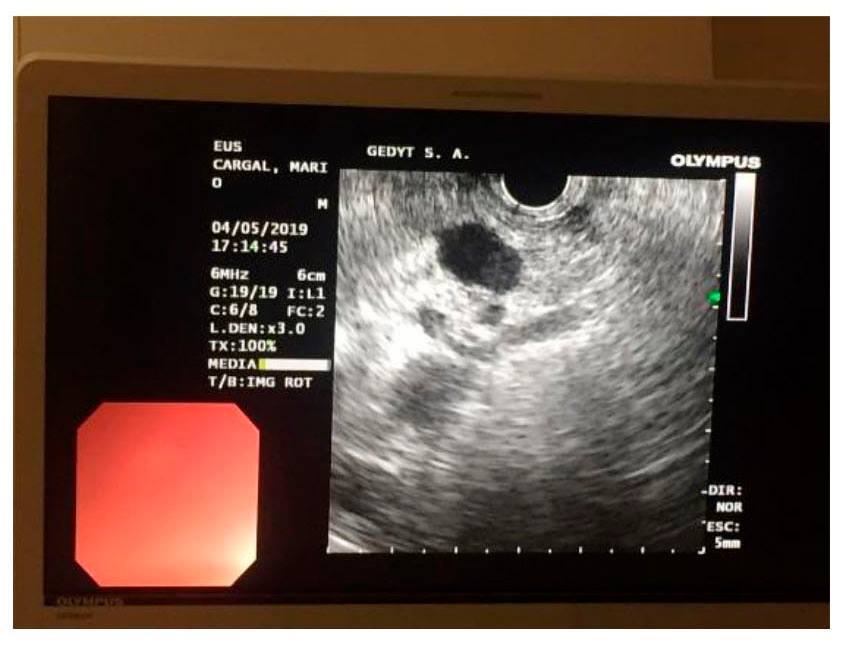

Desde la secretaría de Salud y la dirección del hospital, a cargo de los Dres. Sergio Valente y Nora Grinberg, respectivamente, informaron que se trata de una paciente que tenía diagnóstico de una lesión orgánica de porción cefálica de páncreas, con compromiso de vía biliar condicionando un síndrome coledociano y colangitis. Y precisaron que bajo anestesia general, se hizo la ecoendoscopía lineal con punción y confirmación de obtención de material para examen anatomapatológicointra-procedimiento, habiendo un patólogo en la sala.

El ultrasonido endoscópico o ecoendoscopía es una técnica en la que se combinan en una sola exploración la observación endoscópica directa con la información que aporta el ultrasonido sobre las capas de la pared intestinal subyacentes a la mucosa y los órganos adyacentes.

Existen distintos equipos para la realización de este tipo de procedimientos, y dentro de éstos se encuentran los lineales o sectoriales, que facilitan no solo la obtención de imágenes diagnósticas sino que están dotados de un canal que permite pasar, en tiempo real, instrumental para realizar procedimientos intervencionistas guiados por ultrasonido.